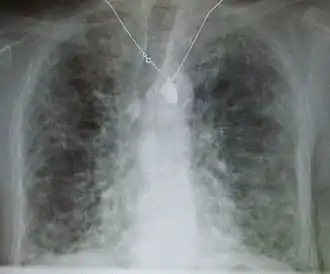

End-stage pulmonary fibrosis of unknown origin, taken from an autopsy

Pneumocystis pneumonia can present with interstitial lung disease, as seen in the reticular markings on this AP chest x-ray.

A chest X-ray demonstrating pulmonary fibrosis due to amiodarone